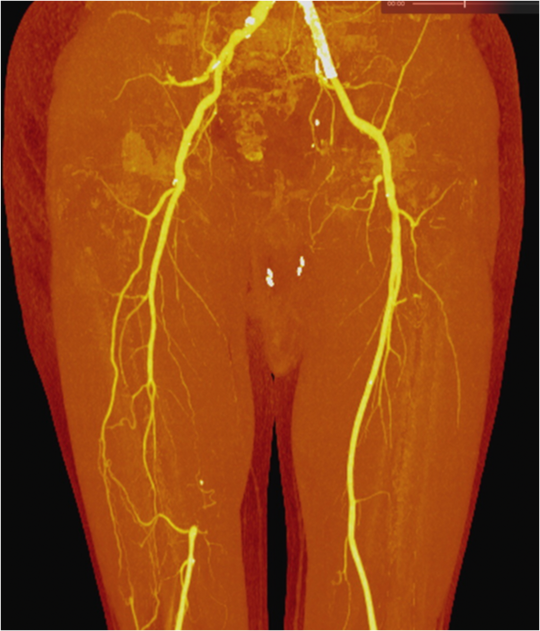

Jeff Carr, M.D., Professor and Cornelius Vanderbilt Chair, Radiology and Radiological Sciences, says the ability to scan with two energies at the same time allows for precise tissue characterization and the ability to remove bones and metal artifacts that can obscure imaging of critical structures.

Examinations of the blood flow to the leg can be performed with both high resolution and lower amounts of intravenous contrast media, which is important for patients with reduced kidney function.